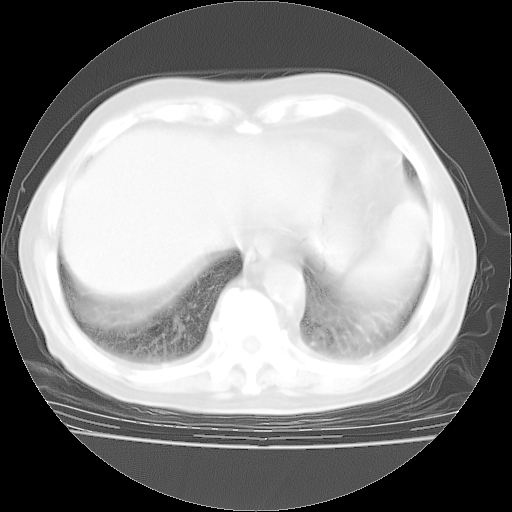

4月28日肺部CT——再次出现类似去年5月9日——磨玻璃样、间有“粟粒样”改变。